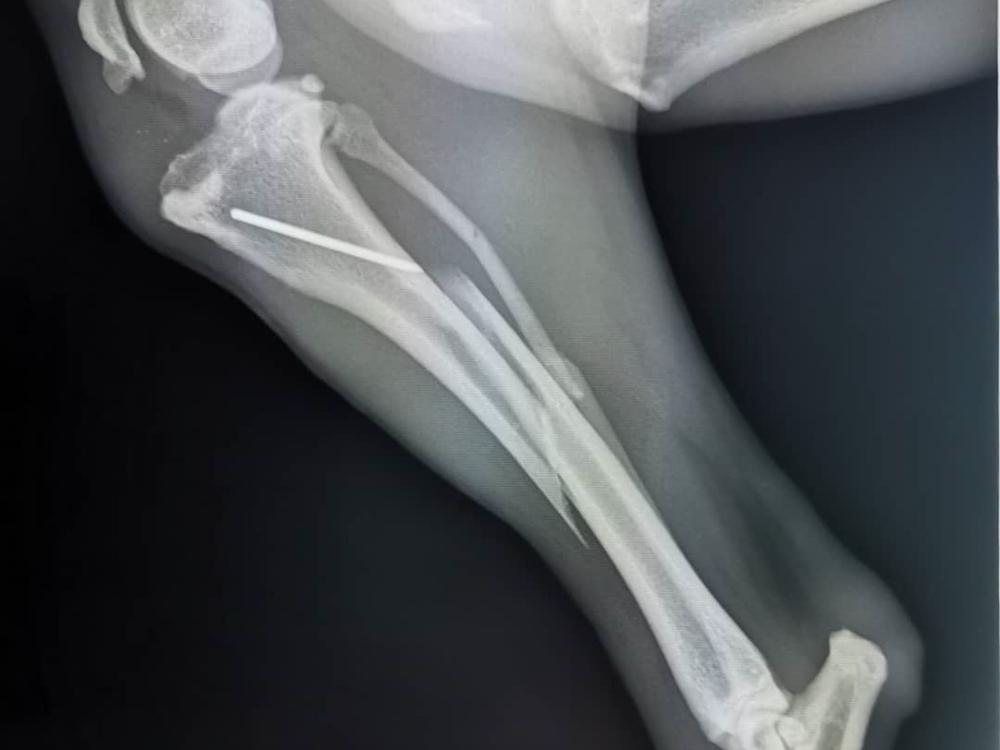

Kay Dog needs emergency surgery on her rear leg that is broken in three places.

You may or may not have heard that Andre's sweet Kay Dog had an accident this week.  She broke her rear leg in three places jumping out of the back of Andre's car.  This is the same leg she had surgery on last year.  Poor thing.